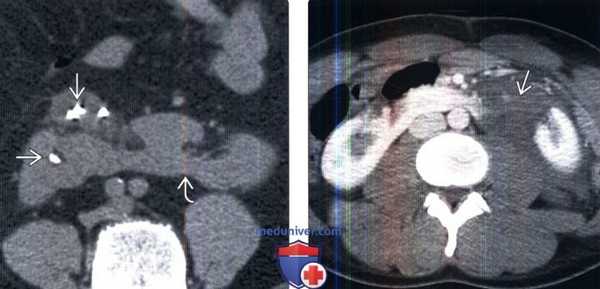

(Слева) КТ без контрастирования, аксиальная проекция: подковообразная почка с множественными конкрементами и рубцевание коркового вещества.

(Справа) КТ с контрастированием, аксиальная проекция: крупный разрыв левой части подковообразной почки с окружающей его гематомой.

(Слева) КТ с контрастированием, аксиальная проекция: крупное объемное образование, занимающее большую часть перешейка и левой части подковообразной почки. Установлено, что это ПКР.

(Справа) КТ с контрастированием, коронарная проекция: у трехлетнего мальчика выявлено крупное гетерогенное объемное образование, исходящее из левой части подковообразной почки. Установлено, что это опухоль Вильмса.